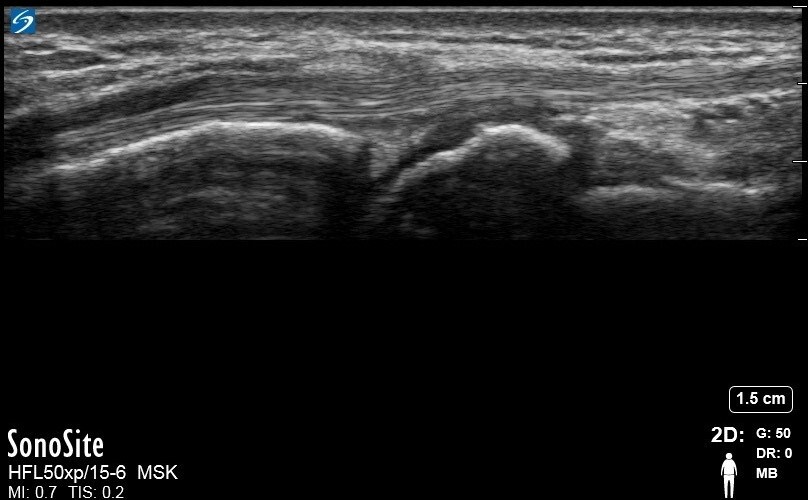

Wrist Compartment Two ECRL Image